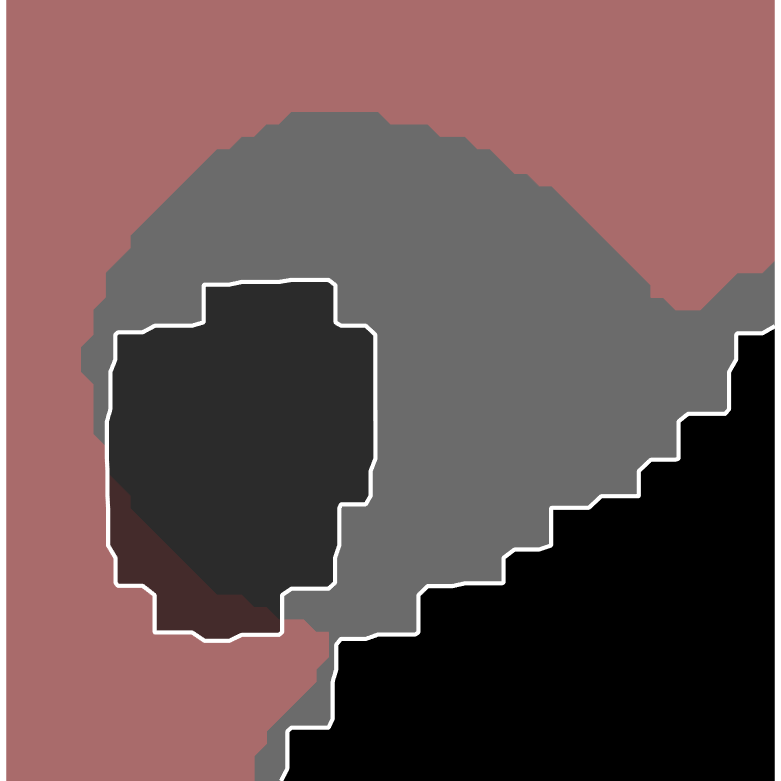

In order to show the advantage of the ensemble, we chose a small, notoriously difficult, region to zoom on: vena cava superior (the blue rectangle in the U-Net plot in Figure 1). Figure 2 contains five plots of the segmented region. The product combiner was chosen for the ensemble. The ground truth is shaded in blue in the ensemble plot, and in red in the plots for the individual segmenters. The guessed segmentation is overlaid in transparent grey. The Dice score for the chosen area is shown under each plot. A Dice score of 1 indicates perfect segmentation while lower values indicate mismatch. As the results show, both visually and through the numbers, the ensemble segmentation is better than any of the individual ones.

| Ensemble | U-net | Deepmedic | V-Net | Dense V-Net |

|

|

|

|

|

| 0.7306 | 0.7003 | 0.5265 | 0.6175 | 0.5863 |